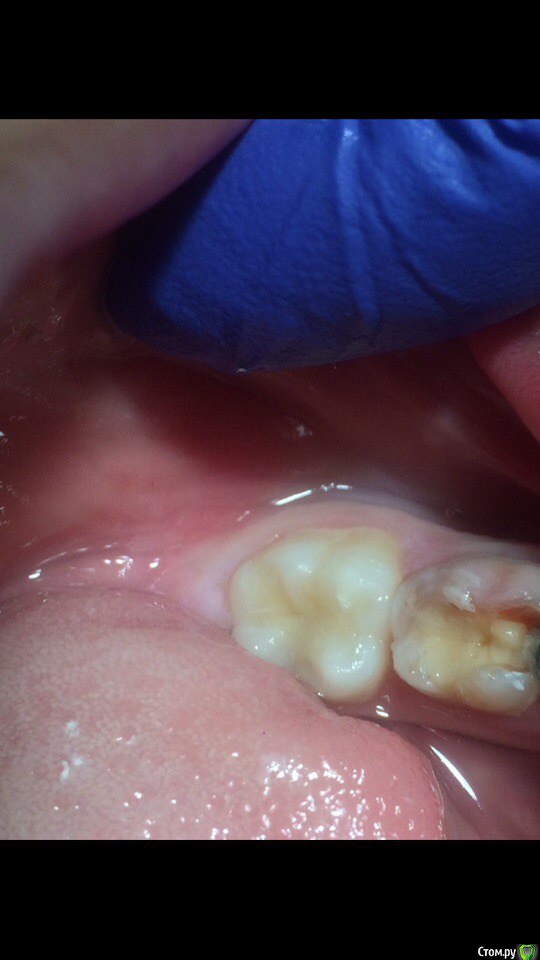

Wrestrus66 Опубликовано 12 октября, 2016 Поделиться Опубликовано 12 октября, 2016 ещё раз всем привет..стаж работы пол года..и вот одна из проблем это 6 в возрасте от 6-12 лет ..не получается делать проводниковую ищу другие выходы..По фото правильно ли я выбираю место вкола инфильрата и сосочки??я уже не знаю что и делать.. Именно туда уколол я и всё равно где эт черная пигментация пациент испытывал сильную прям боль Ссылка на комментарий

Wrestrus66 Опубликовано 12 октября, 2016 Автор Поделиться Опубликовано 12 октября, 2016 вот фото т.е с вколом Ссылка на комментарий

krokomot Опубликовано 12 октября, 2016 Поделиться Опубликовано 12 октября, 2016 у детей при проведении проводниковой анестезии на нижней челюсти нужножно колоть ниже так как нерв располагается немного ниже, это связано что отверстие входа нерва располагается над зоной роста нижней челюсти с возрастом поднимается выше. Ссылка на комментарий